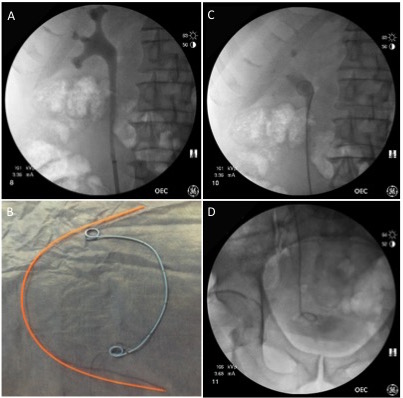

Neuromodulation for Overactive Bladder

- Use of neuromodulation in overactive bladder

- Expanding indications for sacral neuromodulation

- Future technologies in development